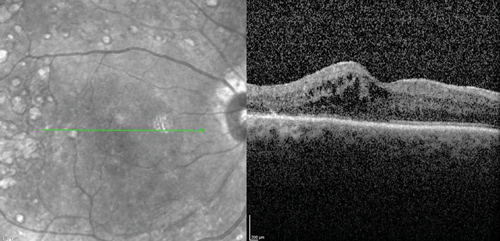

The clinical efficacy and safety of the drug have been also reported in two case reports of vitrectomised eyes with persistent DMO with both cases showing a desirable anatomical outcome. In one case, the authors have suggested that vitrectomy seemed to have enhanced the performance of the implant in-situ and achieved complete DMO resolution [19]. In a recently presented series of 20 post PPV eyes of 18 patients treated with Iluvien, a mean change of BCVA of +9 ETDRS letters (range -6 to +27) as well as mean reduction of CRT by -224µm (-595 to +126) were reported after a mean follow-up period of 201 days (range: 45 to 367 days) (SFO Paris 2016). Further real-life data of Iluvien in vitrectomised eyes with comparable clinical outcomes are awaited with interest. The author’s experience with the drug so far is in-keeping with published cases (Figure 1).

Figure 1 (b).

Figure 1: Case study for management of post-vitrectomy refractory DMO: (a) Pre-vitrectomy; (b) Post-vitrectomy; (c) Post six intravitreal anti-VEGF treatment with sub-optimal response; (d) Post-Iluvien one month. Complete resolution of DMO; (e) Post-Iluvien 10 months. Maintained response to treatment. (Courtesy of Mr David H W Steel - Sunderland Eye Infirmary).